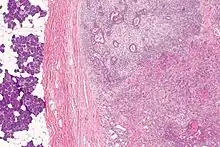

| Micrograph of a carcinoma ex pleomorphic adenoma. The carcinoma component is on the lower right of the image. Benign parotid gland is seen at the left and pleomorphic adenoma is seen at the upper right. H&E stain. | |

Carcinoma ex pleomorphic adenoma (ca ex PA) is a type of cancer typically found in the parotid gland. It arises from the benign tumour pleomorphic adenoma.

Carcinoma ex pleomorphic adenoma is diagnosed by examining it under the microscope with consideration of the individual history.

In approximately 75% of cases ca ex PAs arise in a pleomorphic adenoma that is apparent when the tumour is excised.[2] In the other approximately 25% of cases the individual had a pleomorphic adenoma excised previously and the diagnosis is made based on (1) the presence of a carcinoma, and (2) the history of a pleomorphic adenoma at that location.